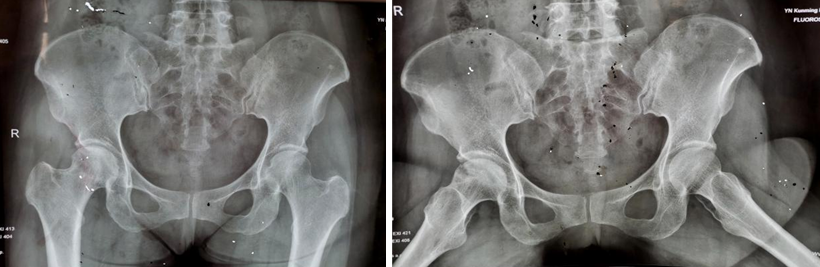

两年多前,34岁的王先生因双髋部疼痛伴活动受限4月余,在家人的搀扶下,一脸痛苦地来到财神捕鱼玩法攻略与赚钱技巧指南 | 财神捕鱼游戏网 骨科就诊。杨振东副主任医师接诊了这位患者,该患者饮酒史10年,每日2两,戒酒1月,右髋外旋活动受限,左髋活动正常,右髋“4”字试验阳性,结合影像学资料显示,该患者右侧股骨头凹凸不平、黯淡无光,且有部分塌陷,诊断为右侧股骨头坏死。

入院3天后,杨振东医师为该患者进行了吻合血管的游离腓骨移植手术治疗。患者全麻生效后取右侧仰卧体位,杨振东医师先从患者身上取长约8CM带血管蒂骨,然后进行股骨头病灶彻底清除,最后截取合适长度游离腓骨,植入股骨颈内,吻合游离雕骨血管至旋股外侧动静脉。手术持续约6小时,手术顺利,患者复苏后安返病房。

术后12个月和24个月,患者来院复查,影像片子显示患者右侧股骨头髋臼平整光滑,股骨头圆润光滑,股骨头内骨小梁密度均匀,已恢复至正常股骨头状态,几乎与正常人股骨头无异。患者随访时说:“来财神捕鱼 之前,我独立行走都困难,短短几米的距离,我可能要花费三四分钟才能走完。手术之后,我不仅可以健步如飞,还能做下蹲等动作,也不必担心重体力劳动导致股骨头无法承受的问题,这个手术真的是太好了,不仅救了我,也救了我一家人……”